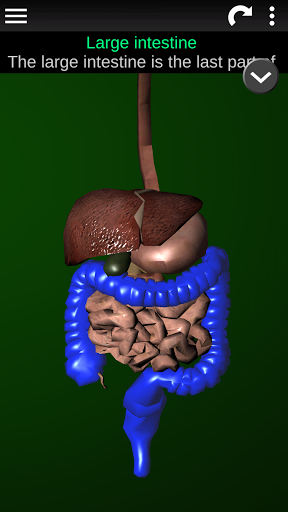

Menampilkan model anatomi 3D dari organ utama tubuh manusia dan penjelasannya masing-masing.

* Sistem pencernaan, termasuk lambung, usus kecil, usus besar, dan animasi sistem ini.